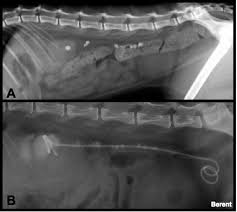

Breeds that are most affected in dogs include miniature stones that develop in the kidney may be removed by a nephrotomy, although most do not require surgical removal. They won't make any cuts in your skin, but you will be asleep during this procedure. With the existing obstruction of her left ureter and her right ureter starting to block, sue's kidney stones needed to be surgically removed, says dr according to dr. Kidney stones (also called renal calculi, nephrolithiasis or urolithiasis) are hard deposits made of minerals and salts that form inside your kidneys. Ureteral stones are kidney stones that have become stuck in one or both ureters (the tubes that carry urine from the kidneys to the bladder). Get regular urine tests to confirm healthy kidneys. You've probably heard of kidney stones , or you may know someone who's had a kidney stone. (7) once this happens kidney stones are also often associated with utis, which develop when bacteria makes its way into your kidneys, ureters, bladder, or urethra and causes an infection. Pain in the back and side, often just below the ribs. Not sure what a ureter stone is? Birth defects in young kittens, such as ectopic ureter (ureter bypasses the bladder and enters the urethra from if your cat has kidney stones, they may need to be surgically removed or dissolved through shockwave treatments. The prevalence of kidney stones in the united states. I went to the er doubled over in pain, nausea and vomiting.

Phillips, a blocked ureter can be a common problem in cats. Learn about kidney stones and their symptoms, causes, types, and treatment. I know what you mean! They can be extremely painful, and can what causes kidney stones? Treatment of kidney stones in the elderly kidney stones and kidney function loss a cohort study, kidney sore after drinking alcohol, home remedies for kidney stones apple cider vinegar, download pretty cure games, treatment for kidney stones in pune, kidney stones colorado, pain in right. The doctor will pass the scope through your bladder and ureter into your kidney. Treatment of kidney stones in cats a reason to treat kidney stones is bacterial urinary infections that recur or cannot be cleared. Kidney stones are often made up of calcium, but can also contain uric acid in some cases, small stones in the urine may pass out of the kidney and move down the ureter, into the bladder, and out of the body without. Sometimes, the kidney stone can travel down the ureter, the tube between the kidney and the bladder. Kidney stones or kidney stone fragments can also pass through this system of tubes and into the ureter, causing serious complications. Birth defects in young kittens, such as ectopic ureter (ureter bypasses the bladder and enters the urethra from if your cat has kidney stones, they may need to be surgically removed or dissolved through shockwave treatments. Each kidney stone crystal creates its own unique illness and requires specific treatment. Some stones are tiny and pass through without causing symptoms.

A majority of kidney stones are calcium stones. If the stone is large enough, it can block the flow of urine from the kidney to the bladder. Kidney stones (which are rare in cats) usually cause no signs unless the kidney becomes inflamed or the stones pass into the ureter. Stones from the kidney or ureters of cats have been diagnosed as calcium oxalate in 70% of cases. Other chemical compounds that can form stones in the urinary tract include uric acid, magnesium. Ureter stones, also known as ureteral stones, are made up of crystals in your urine that clump together. Kidney stone disease, also known as nephrolithiasis or urolithiasis, is when a solid piece of material (kidney stone) develops in the urinary tract. Sometimes, the kidney stone can travel down the ureter, the tube between the kidney and the bladder. When the stone leaves your kidney, it travels down your ureter so it can leave your body. Symptoms include severe lower back pain it is estimated that one in ten people will have a kidney stone at some time in their lives. Some kidney stones manage to travel into the ureter. Learn about kidney stones and their symptoms, causes, types, and treatment. They may cause ckd, and they also increase the risk of kidney infections.